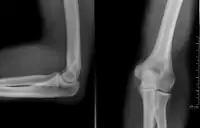

پَرتونِگاری[1] یا رادیوگرافی (به فرانسوی: Radiographie) شیوه بررسی بدن با تاباندن پرتوهای ایکس بر آن و تولید تصویرهایی بر روی کلیشه یا پردههای حساس را گویند.

پرتونگارها یا رادیوگرافها که به آنها «رونتگنوگراف» هم میگویند، و پس از کشف پرتوهای ایکس (اشعه ایکس)، توسط «ویلهلم رونتگن» مشهور شدند، توسط انتقال اشعه ایکس از میان بدن بیمار به یک دستگاه ضبطکننده و سپس تبدیل آن به یک تصویر برای تشخیص، پدید میآیند. در اصل [یعنی در زمان اختراع این شیوه] و در حال حاضر هنوز هم بهطور معمول، تصویرها بر فیلمهای آغشته به نقره یا اشباع شده با آن ثبت میشوند. در رادیوگرافی نوع «فیلم. اسکرین» (فیلم -- صفحه) یک لامپ اشعه ایکس، تولید یک بیم یا پرتو از اشعه ایکس میکند که بیمار با آن هدف قرار داده میشود. پرتوهای ایکس از طریق بدن بیمار عبور کرده و به منظور کاهش پراکندگی و صدای اضافی(نویز) از آنها، فیلتره میشوند و سپس بر روی فیلمی به صورت نامرئی ظاهر میشوند، که با یک صفحه از نور ساطع شده از فسفرهایی که در کاست ال. تی light-tight cassette نگه داشته میشود، برخورد میکنند. سپس فیلم به صورت شیمیایی ظاهر میشود و یک تصویر بر روی فیلم به نظر میرسد. در حال حاضر رادیوگرافی دیجیتالی یا DR جایگزین رادیوگرافی فیلم - اسکرین شدهاست. در دیجیتال رادیوگرافی، اشعهٔ ایکس به یک سطح از حسگرها (سنسورها) برخورد میکند که بعد از تبدیل به سیگنالهایی که تولیدکننده اطلاعات دیجیتال هستند به یک تصویر در روی صفحه نمایش کامپیوتر تبدیل میشود. رادیوگرافی ساده تنها تصویر با کیفیت در دسترس، در طول ۵۰ سال اول استفاده از رادیولوژی بوده و هنوز هم به علت دسترسی وسیع، و سرعت و هزینه نسبتاً پایین آن، اولین مطالعه دستور داده شده (تجویز شده) در ارزیابی از ریهها، قلب و اسکلت است.